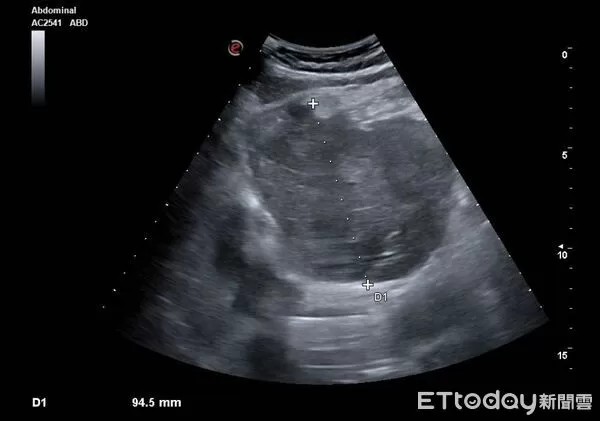

▲老伯肝臟有顆9公分巨瘤,恐是肝癌。(示意圖/CFP)

許多人一出現上腹痛,直覺反應就是「胃不舒服」,以為吃點藥就會好,但這可能是身體發出的求救訊號!胃腸肝膽專科醫師陳保中近日分享,一名80歲老伯上腹痛了整整一個多月,原以為是胃病,怎料進一步檢查,竟在肝臟發現一顆9公分巨瘤,影像看起來高度懷疑是肝癌,且隨時有破裂風險,當下不敢耽誤,緊急轉送急診救治。

陳保中醫師在粉專「Dr.陳保中《健康減重,腸胃保安康》」指出,這名老伯主訴上腹部疼痛已經持續一個多月,曾前往其他診所看診拿藥,但服用後症狀卻完全沒有改善。患者後來轉診求助,醫師察覺不對勁,立即替他安排腹部超音波檢查,影像顯示左側肝臟竟然有顆「9公分大的腫瘤」,高度懷疑是肝癌。